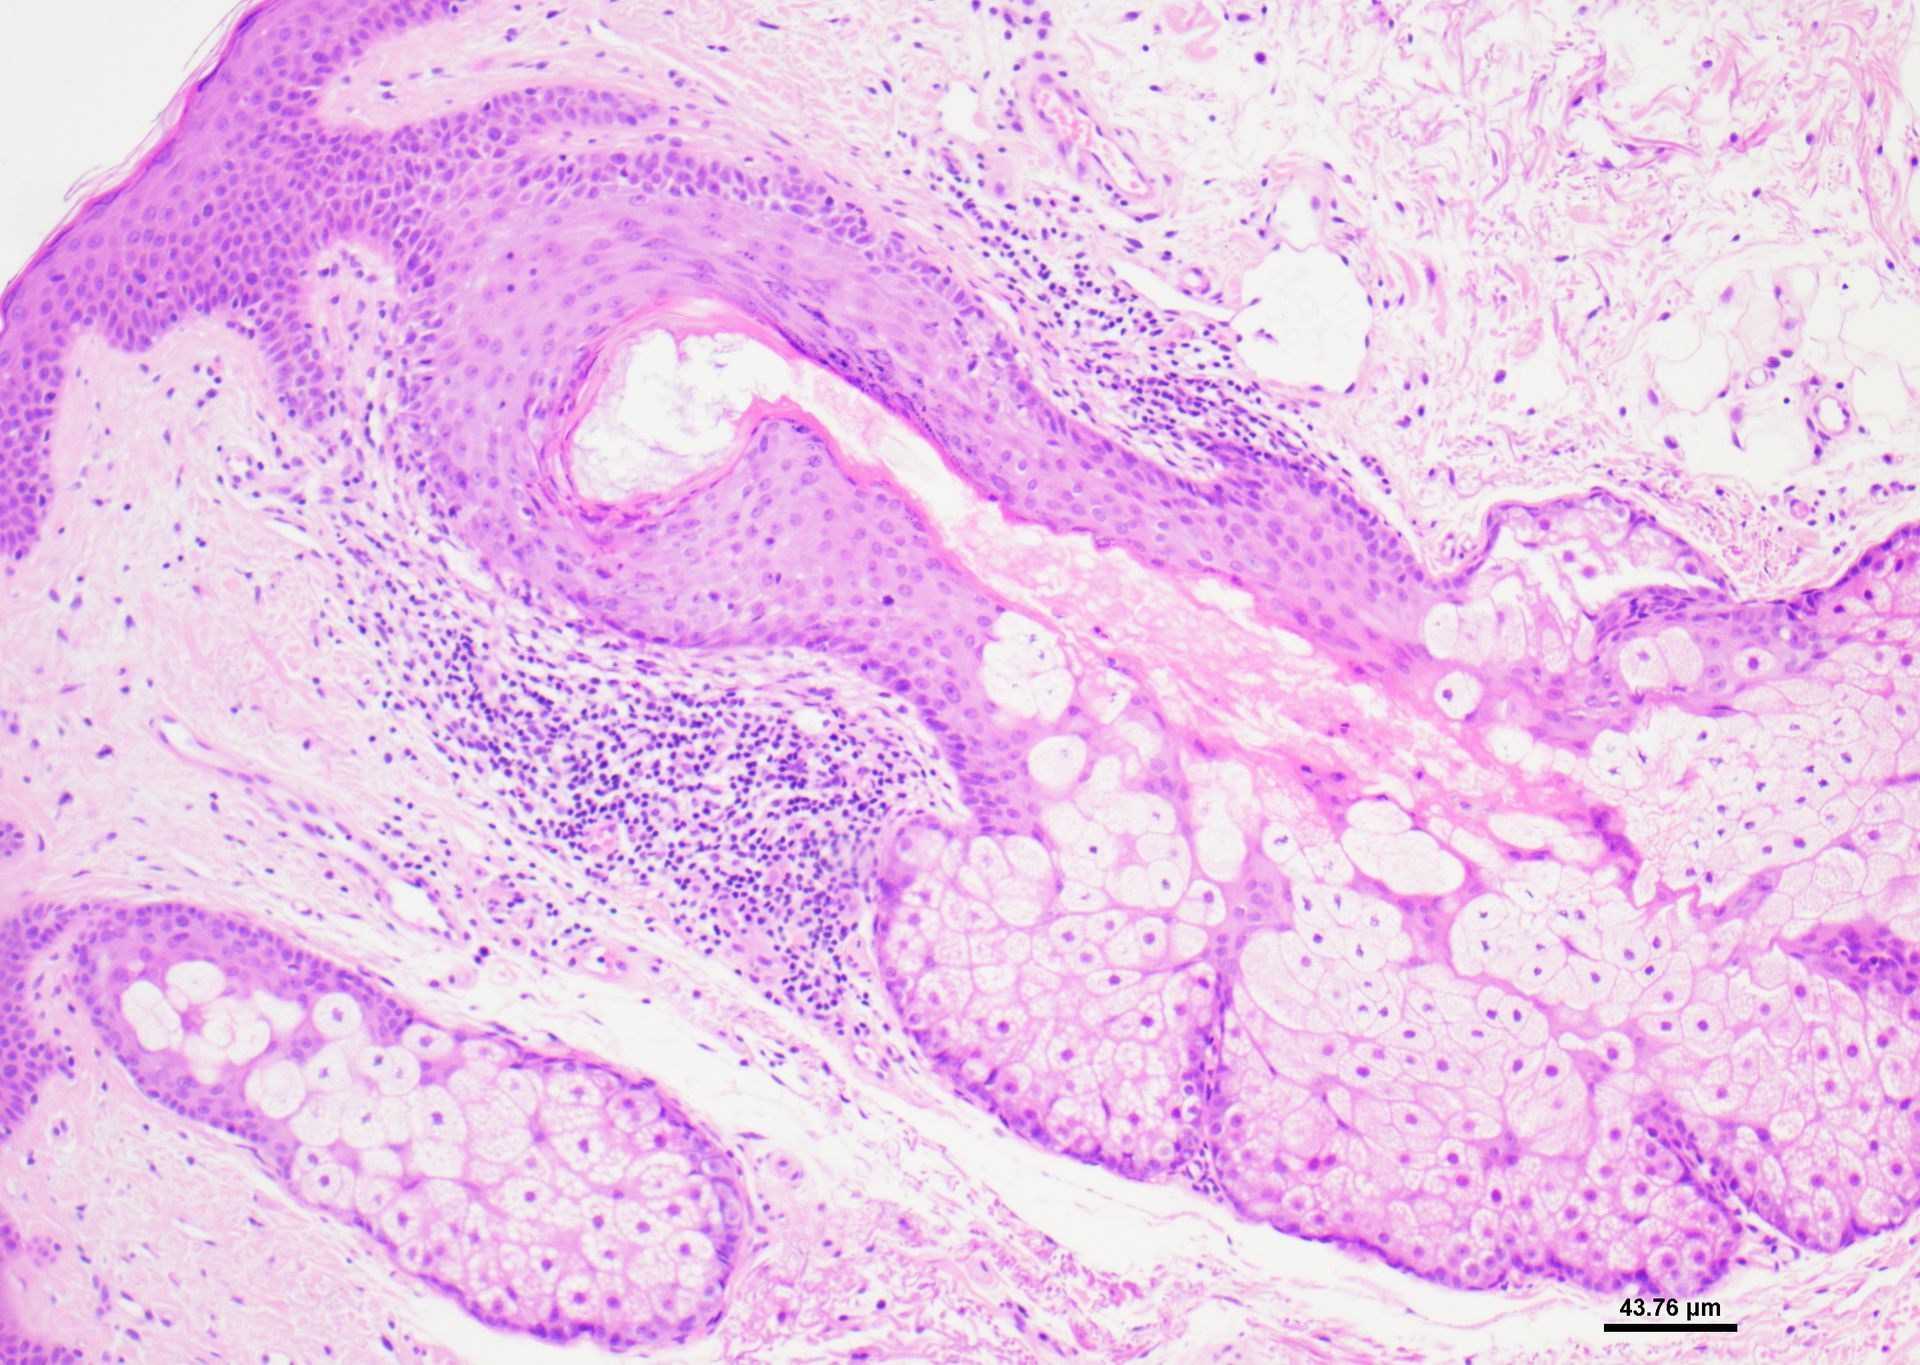

- Διαγνωστικές ημιλεπτές τομές ρητίνης